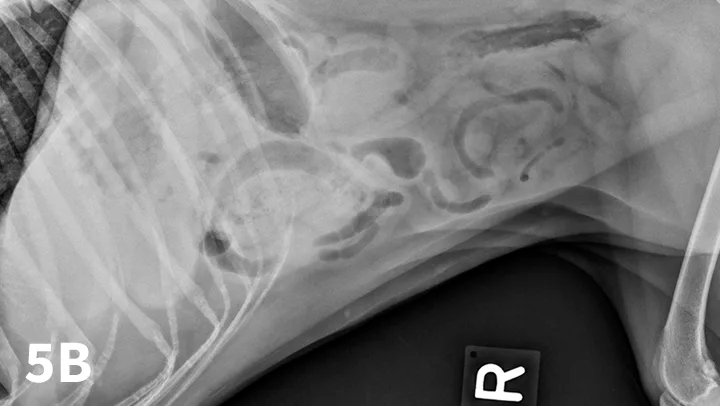

Figure 5A depicts a left lateral abdominal radiograph of a dog with a pyloric foreign body. Figure 5B depicts a right lateral abdominal radiograph of a dog with a pyloric foreign body.

Left lateral radiograph (A) of a 4-year-old crossbreed dog with a 3-day history of vomiting and anorexia. An irregularly marginated, well-defined, soft tissue opaque structure (arrows) outlined by gas is present within the pylorus on the left lateral view. A right lateral radiograph of the same dog (B). The irregularly marginated, well-defined, soft tissue opaque structure displayed in Figure 5A is not clearly seen on the right lateral view because of the dependent distribution of fluid into the pyloric antrum silhouetting with the foreign body. This was confirmed to be cloth causing a gastric outflow obstruction.